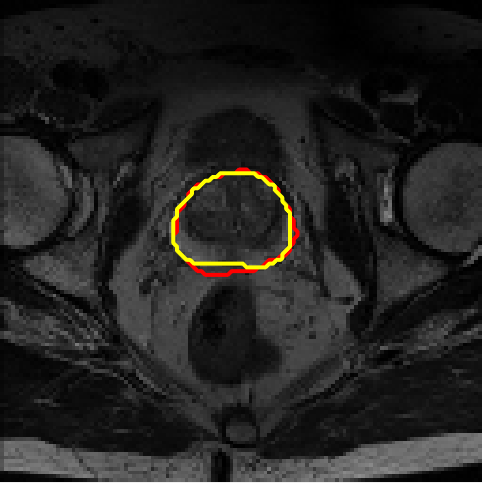

4.4 Results on PROMISE12

We assess different semi-supervised methods on the PROMISE12 dataset (Litjens et al., 2014). The PROMISE12 dataset contains 50 transverse T2-weighted MR images with the most anatomical detail. 35 and 15 cases are randomly selected for training and validation. The images were resized to 128×128128\times 128. The training dataset includes nn fully annotated images, with pixel-wise labels unavailable for the remaining 35n35-n. Table 3 presents the results. Fig. 7 offers a visual comparison of the segmentation results for different models and shows that the proposed method achieves more precise segmentation.

Figure 7: Example segmentation obtained by different methods on the PROMISE12 dataset. Red lines indicate predicted results, and yellow lines indicate ground truths.